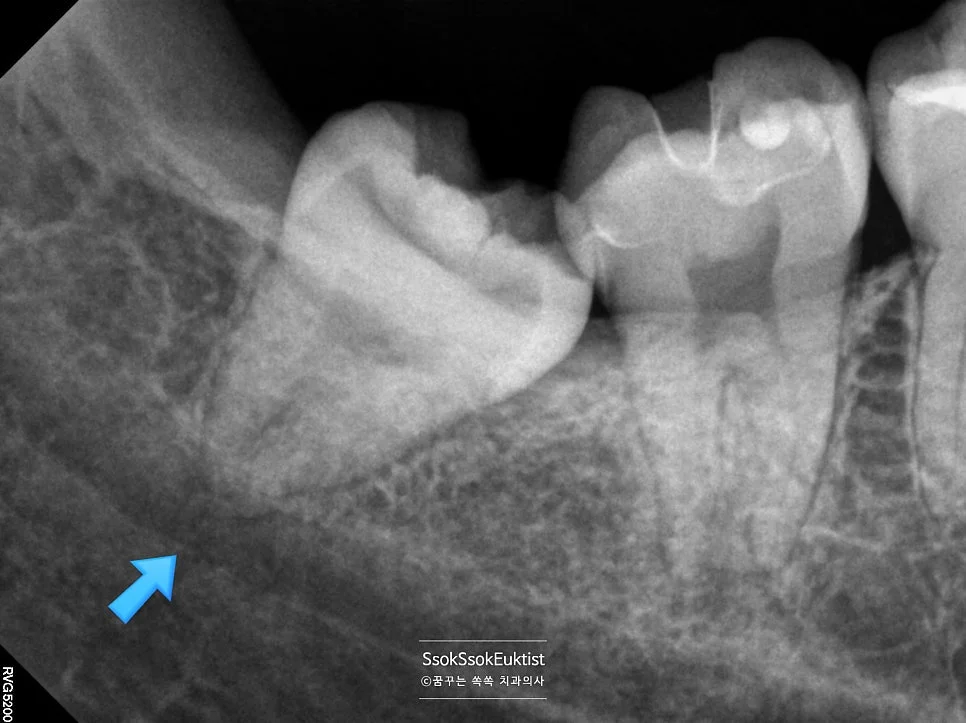

교익 방사선 사랑니 인접 충치 빨간 표시

교익 방사선(Bitewing X-ray) 사진 — 빨간색 표시 부분이 사랑니로 인해 생긴 충치

왼쪽 아래 사랑니를 촬영한 교익 방사선(Bitewing X-ray) 사진을 보면, 빨간색으로 표기한 부분이 충치인데요! 사랑니가 없었다면 절대 생기지 않을 충치입니다ㅜ

사랑니 인접 충치가 특히 위험한 이유

심지어 사랑니 때문에 생긴 충치는 치아 뿌리 쪽에서 시작하는 충치로, 뿌리를 구성하는 치아의 안쪽 재질(상아질)은 무르기 때문에 매우 빨리 충치가 진행하고, 심지어 거리도 신경과 매우 가깝기 때문에 조금만 방치하면 신경치료 및 크라운을 하게 됩니다ㅜ

결국 이 치아는 신경치료 및 크라운을 시행하게 됩니다. 여러분, 사랑니는 제발 아프기 전에 빼주세요ㅜ